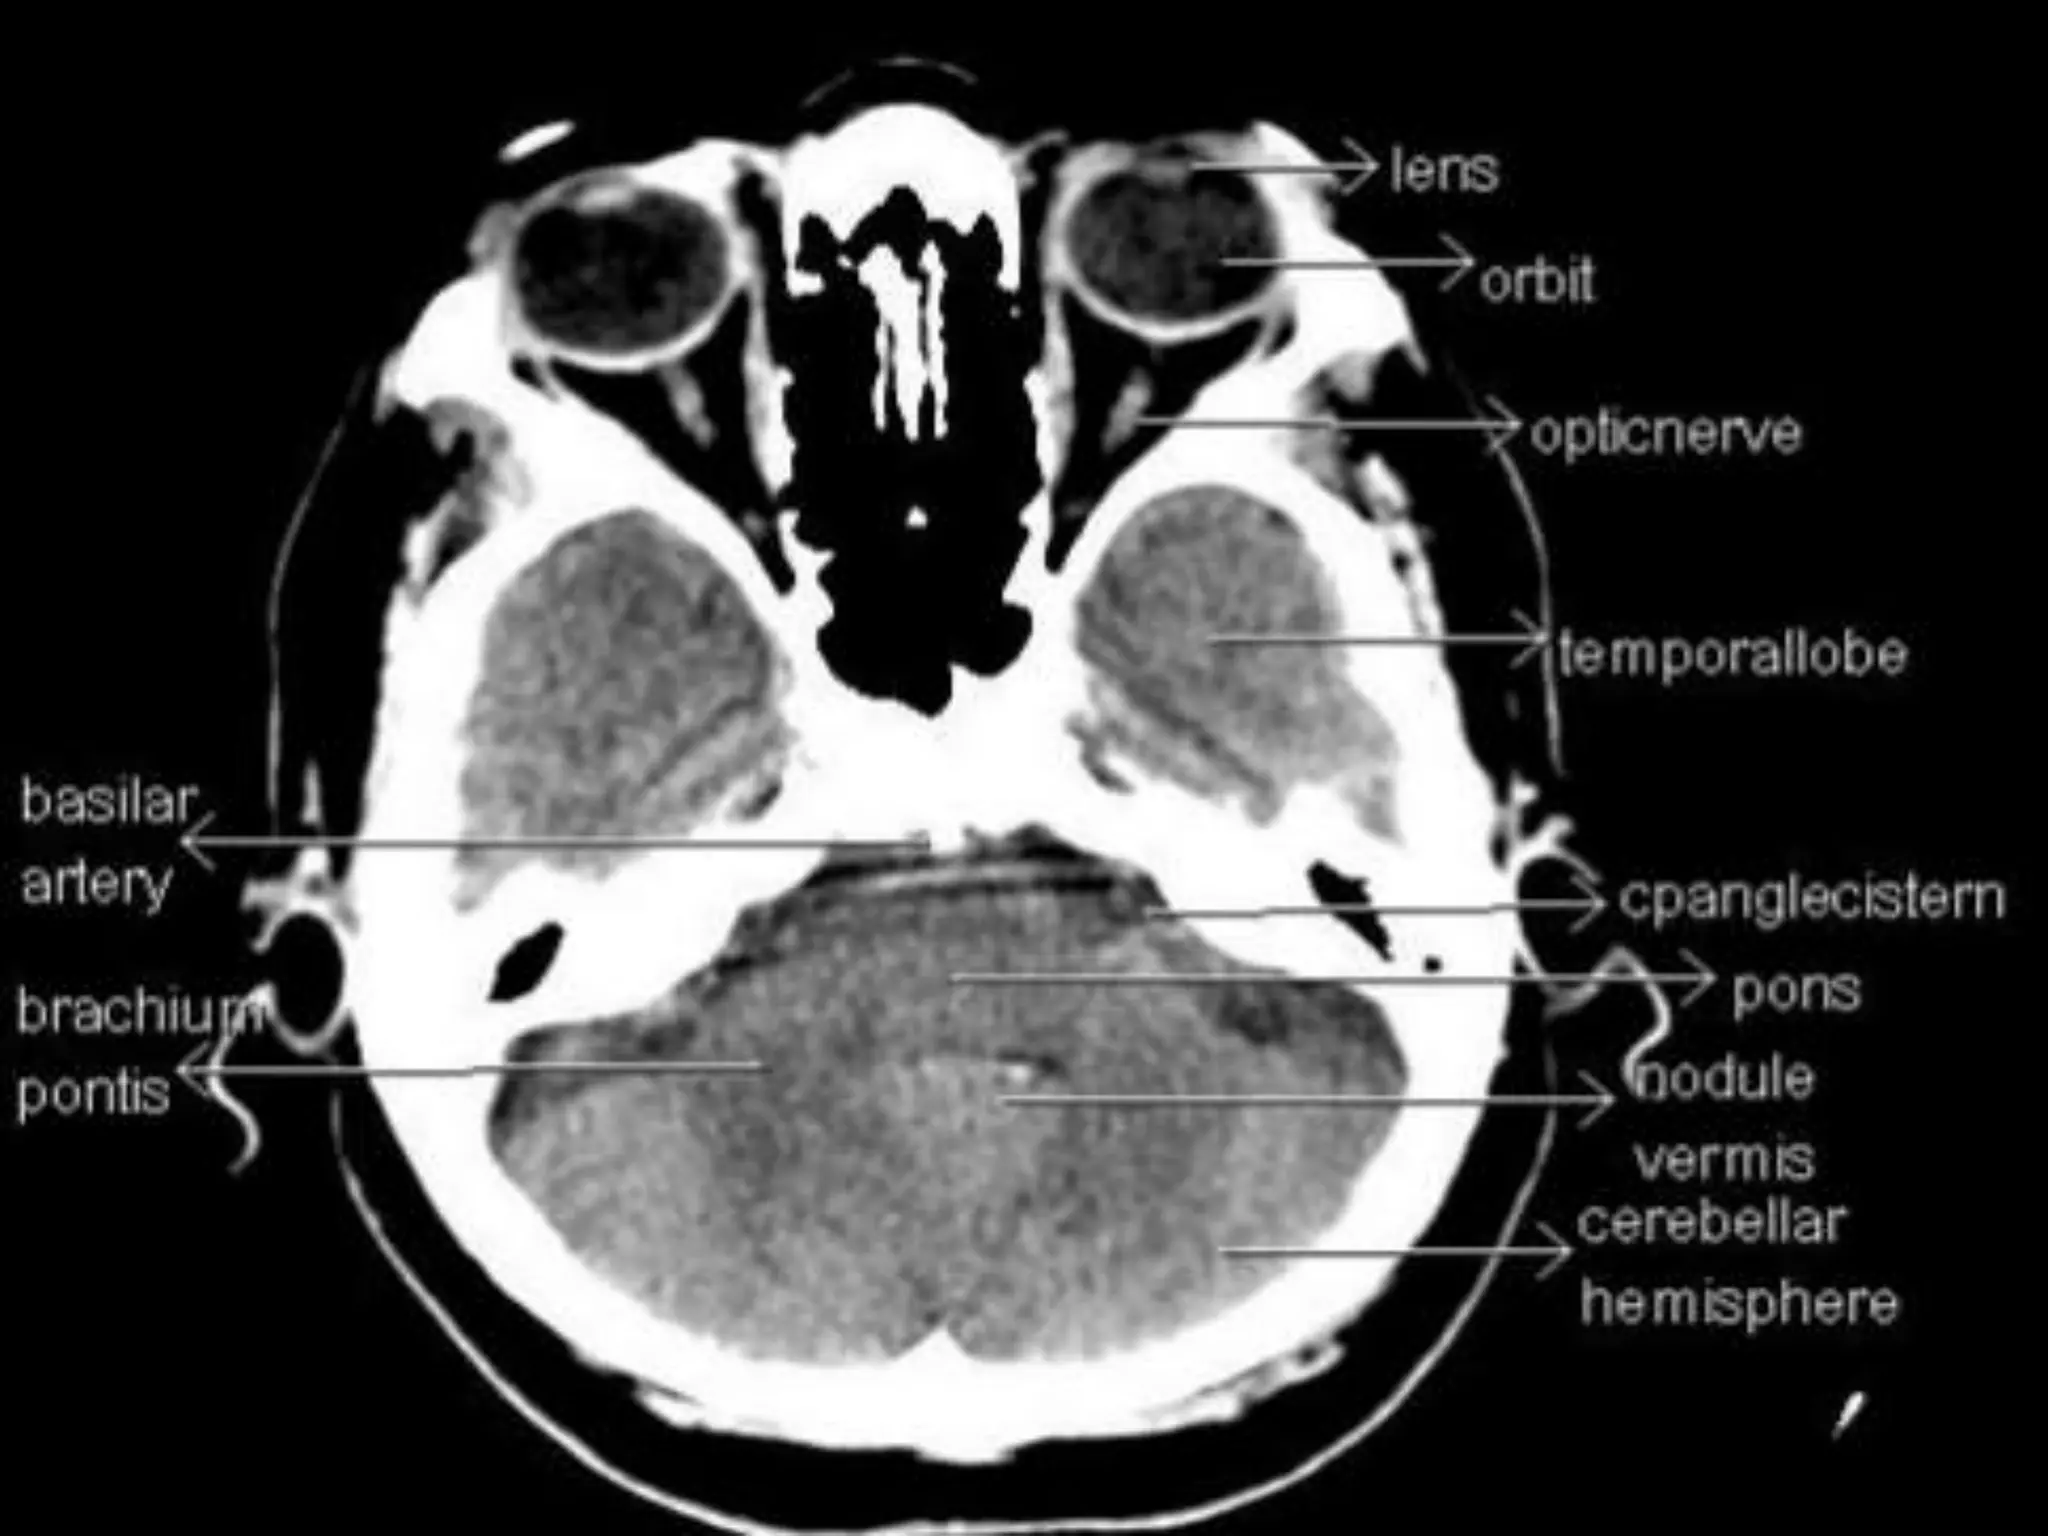

Axial CT Anatomy.

In the parietallobe, there are a postcentral gyrus, a superior parietal lobule, and an inferior parietal lobule. The postcentral gyrus is a primary somesthetic area involved in general body sensation. In the temporal lobe, the superior, middle, and inferior temporal gyri are separated by the two transverse sulci. The posterior fossa contains the cerebellum and brain stem. The posterior fossa is outlined by the clivus and petrous bones anteroinferiorly, the tentorium cerebelli superiorly, and the occipital bone posteroinferiorly. The cerebellum is located posteriorly in the two thirds of the posterior fossa, separated from the brain stem by the fourth ventricle. The brain stem occupies the anterior third of the posterior fossa, including the midbrain, pons, and medulla oblongata. The brain derives its vascular supply via two carotid and two vertebral arteries. The internal carotid artery bifurcates terminally into the anterior and middle cerebral arteries. The two vertebral arteries unite at the caudal border of the pons to form the basilar artery.

Sectional Anatomy: NormalAxial CT and MRI Anatomy. On CT and MR scans, the brain has been briefly viewed in infratentorial and supratentorial sections, as described below. CT scans are performed with a 15- to 20-degree angulation to the canthomeatal line at 8-mm increments. MRI scans are generally obtained parallel to the AC-PC line in the axial plane with 6-mm slice thickness. Using the sagittal view, the coronal sections are acquired parallel to the brain stem, and the sagittal sections are obtained perpendicular to the axial section. On MRI studies, cranial nerves IX and X can be demonstrated at this level because they emerge from the postolivary sulcus. The posterior aspect of the cerebellar hemispheres is outlined by the inferior portion of the cisterna magna.